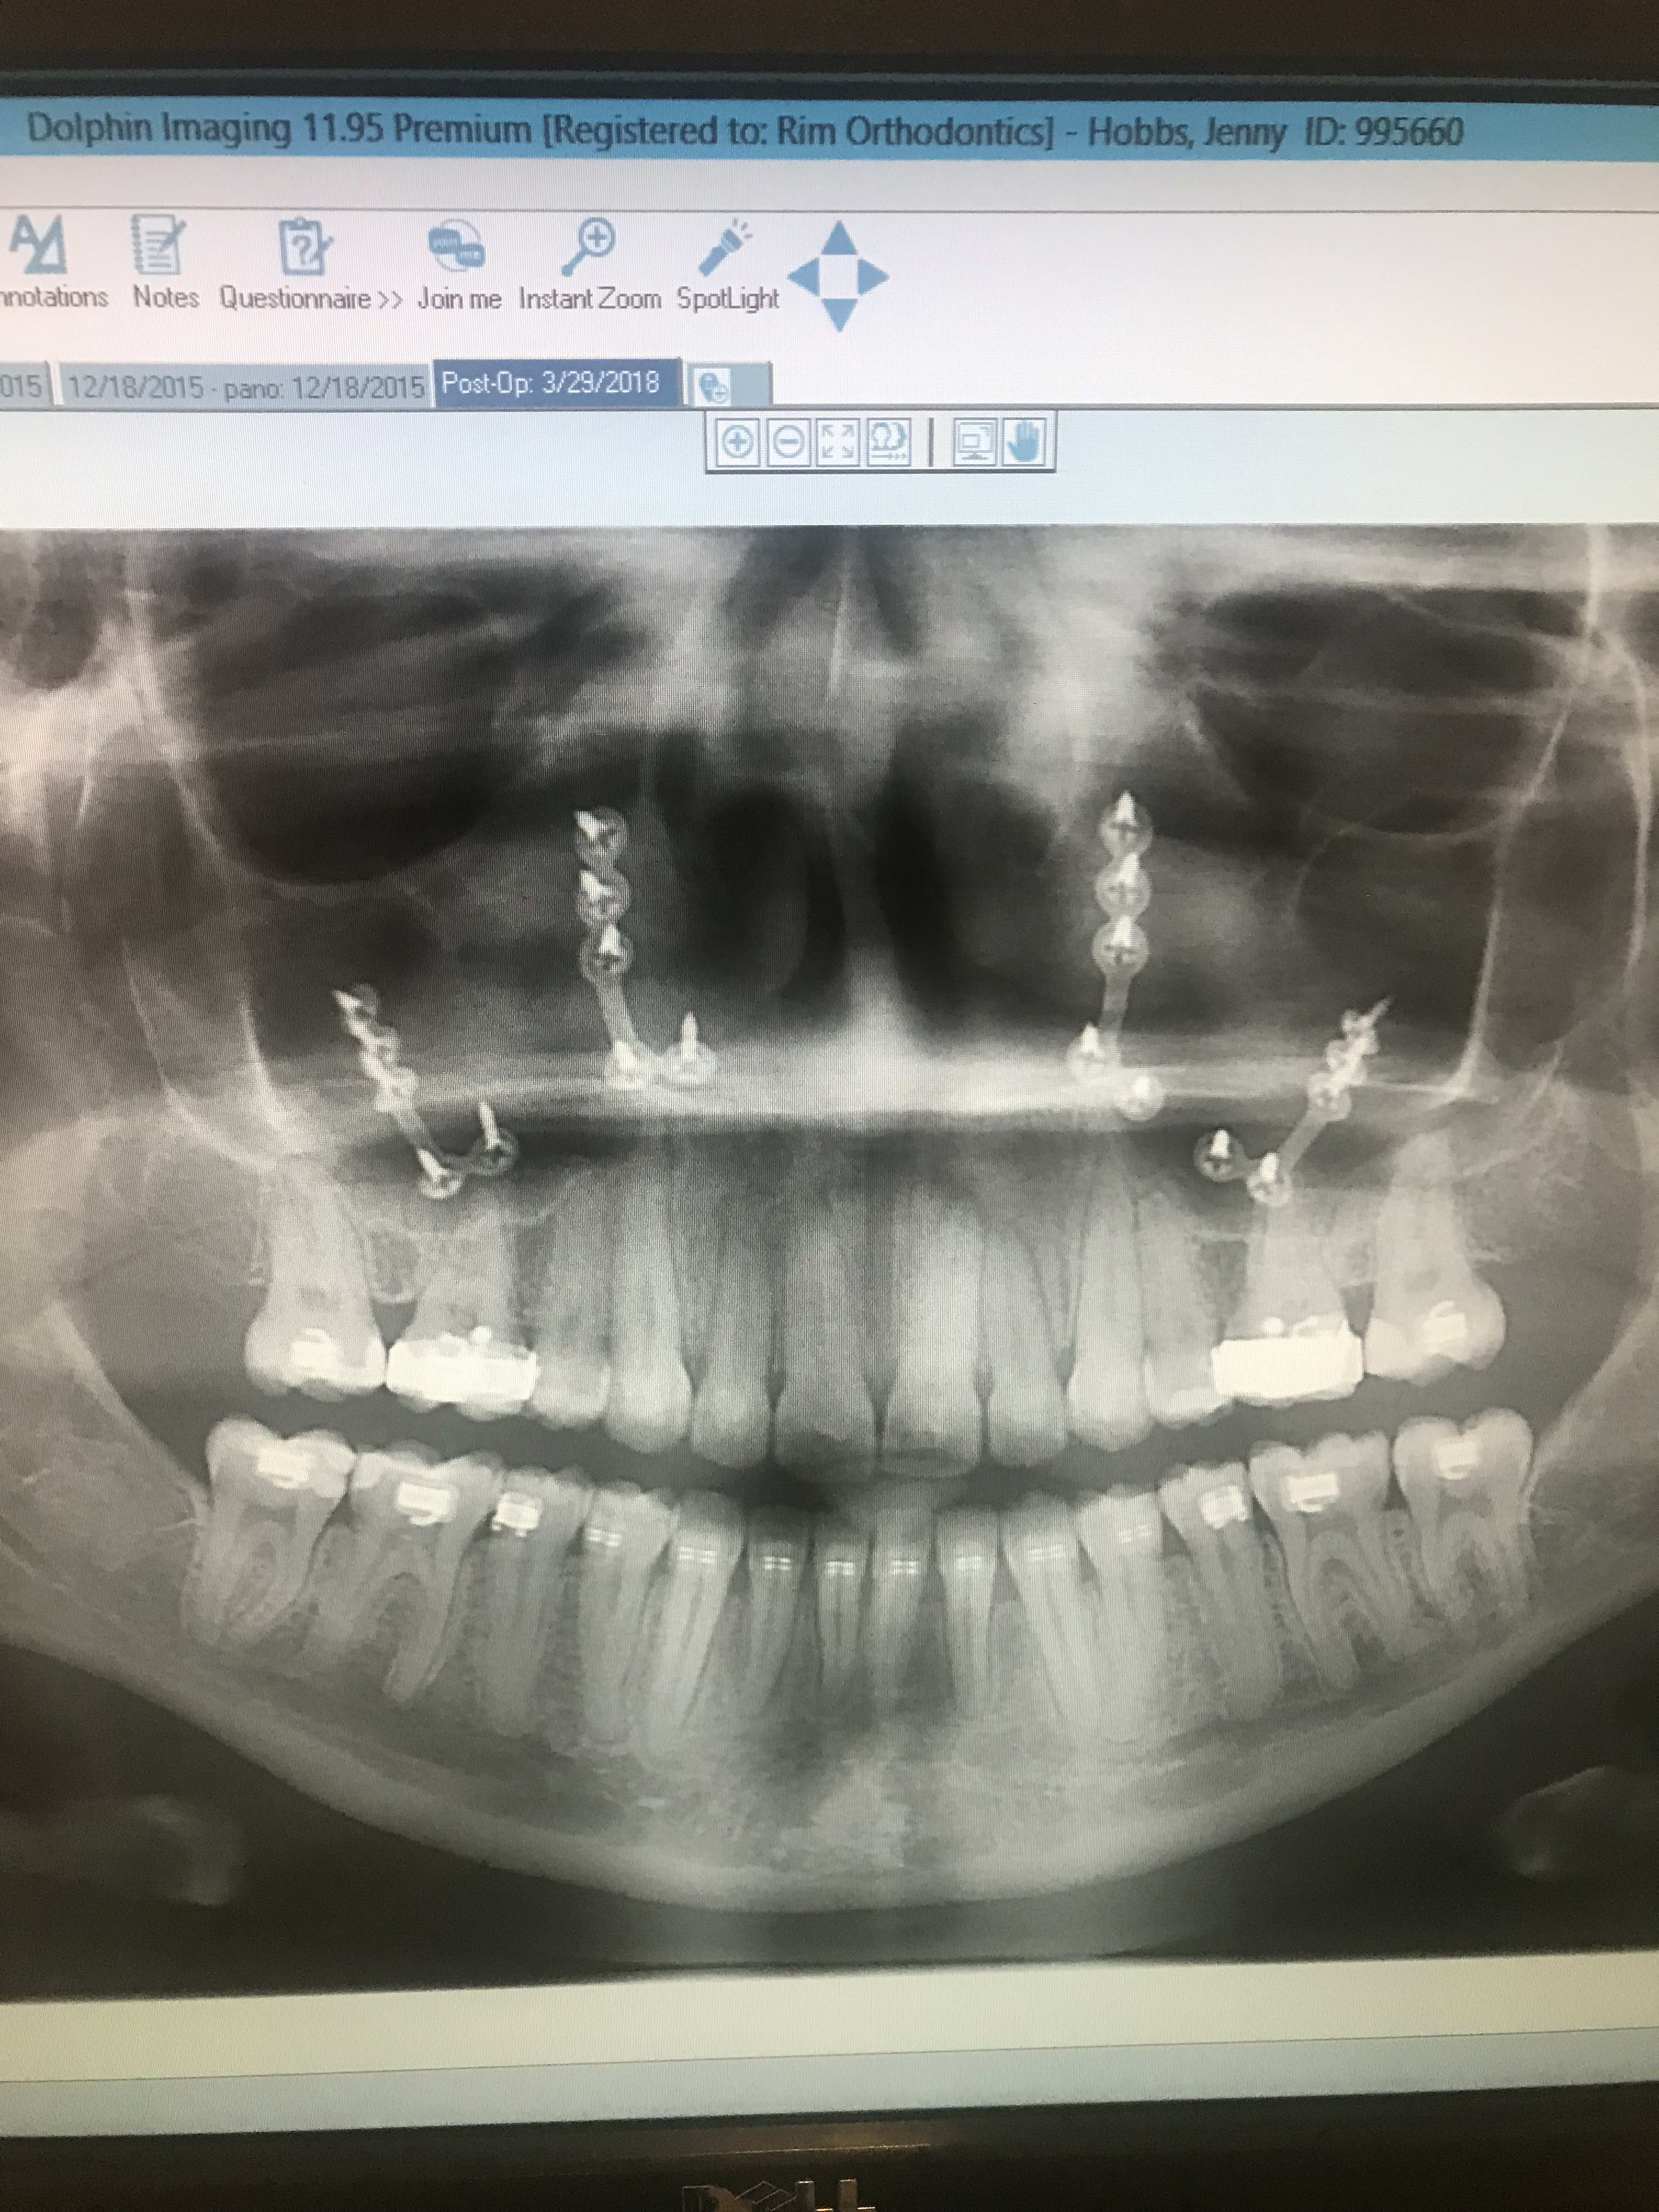

I had surgery to help me with my underbite. The surgery took around 4-5 hours. This is exactly how they did the cut on my upper jaw. It cost around $94k and somehow after the surgery we got another bill for $5k. Thank goodness for insurance! I just wanted to thank Celestine who was the only family member who reached out to me. Celestine sent me so many gift cards to help buy food for the boys. As you can see, I was pretty much out of service. The meds were so strong that I would take them at 7:30am (kiss the boys goodbye) and the next time I would open my eyes Mario was waking me up at 4pm. He had keys. Jared was at work until 6pm. Mario and Milo would take care of each other and make their TV dinners. They watched movies until Jared got home. By the third week I was already lucid. Liquid oxycontin is not a joke. By the second week, I would mix it with bubble gum flavored Children's Tylenol. By the third week, I was so much better.

Celebrating the birthday of my friend Christine Rondon. Mario and his favorite dental assistant. Mario and I with our braces. Another field trip for Milo's class. Mario's 4th grade teacher Ms. Beck. My friend Pramoda. Milo and his bestie Emily.